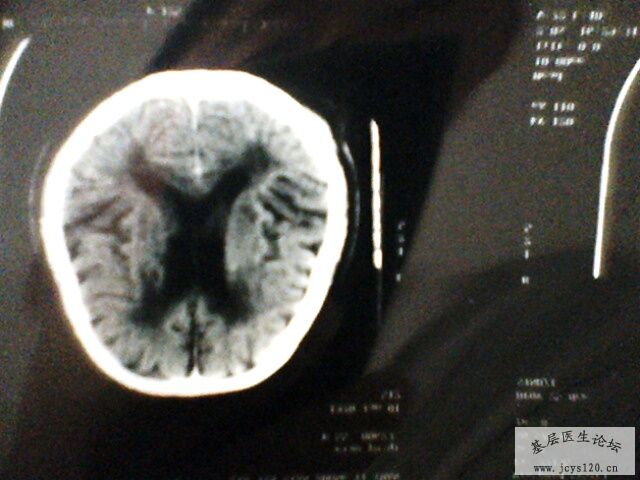

辅助检查:急诊颅脑CT:桥脑处见一卵圆形高密度灶,最大直径1.0cm,右基底节处见多个不足1.0cm大小的低密度灶,侧脑室前后角分布均匀的低密度灶,脑室及脑沟裂未见异常,中线结构居中。 CT意见:脑血肿 皮质下动脉硬化性脑病

病情跟踪报道: 患者今天是输液第十天,瞩患者复查CT,见附件! 患者目前一般情况好,饮食睡眠正常,无头痛头晕,上唇仍感麻木,四肢活动正常,肌力正常,右侧胸痛减轻。病人及家属对治疗比较满意,目前还在继续治疗中 目前输液处方: 5% GS 250 ml 丹参 400mg 5%GS 250 ml 脑复康 5.0 胞二磷胆碱 0.75 门冬 10ml

从患者CT上大家应该可以看出,建议大家对比一下患者发病时的CT片子,桥脑部位的出血(高密度)现在密度降低,上级医院CT诊断为出血吸收期,所以患者目前正在恢复当中!!!!